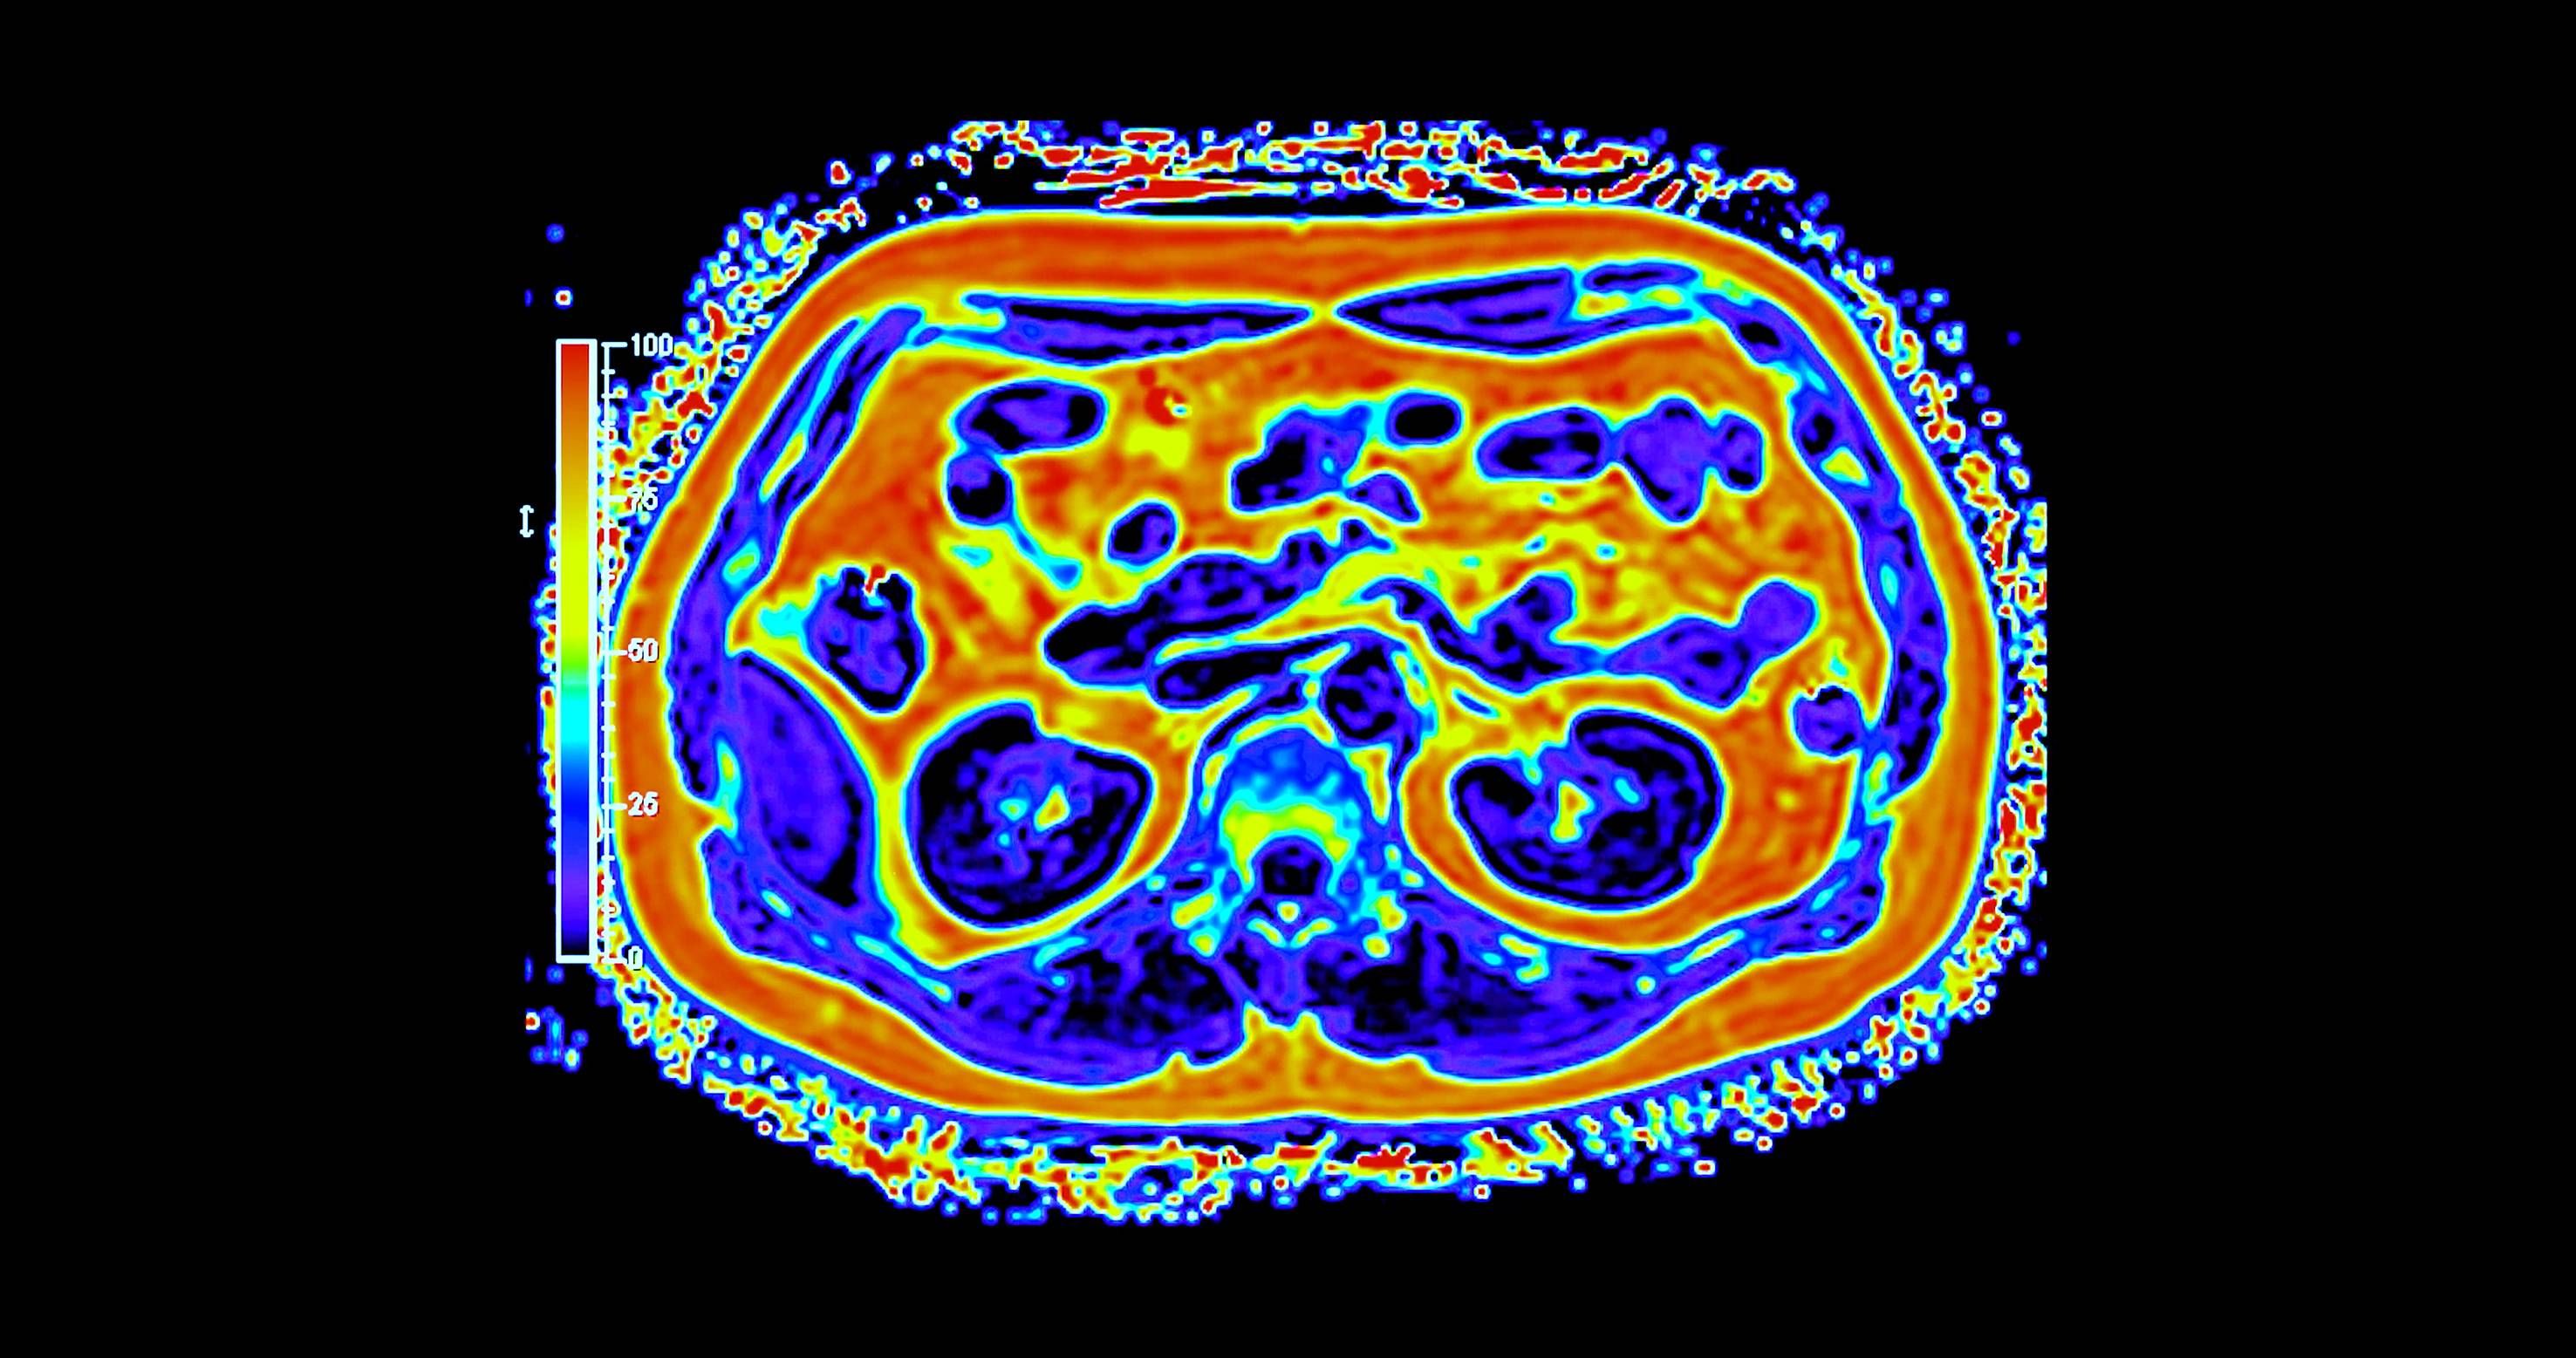

وعلى خلاف التصوير التقليدي، يجمع التصوير الجزيئي بين التفاصيل التشريحية والبيانات الوظيفية الآنية، ما يتيح للأطباء رؤية كيفية عمل الأنسجة لا مجرد شكلها. وفي مجالَي الأورام والأمراض العصبية، قد يُحدث هذا الفرق تحولاً في توقيت الاكتشاف أو في تعديل خطط العلاج أو في تجنّب إجراءات غير ضرورية. غير أن توسيع هذه القدرات عبر بلد واسع ومتنوّع جغرافياً يطرح تحديات تتجاوز كثيراً مجرد اقتناء الأجهزة.

أحرزت السعودية تقدماً تدريجياً في نشر أنظمة التصوير المتقدم، بما في ذلك «PET - CT» و«PET - MRI» داخل مراكز طبية كبرى. وبحسب الدكتور سامح الشيخ المدير العام لشركة التصوير الجزيئي والقطاع الطبي بوادي جدة، أثبتت هذه التقنيات قيمتها السريرية عبر الكشف عن انتشار سرطاني أو اضطرابات لم تُظهرها وسائل التصوير التقليدية، ما أتاح تعديل العلاج فوراً في عدد من الحالات.